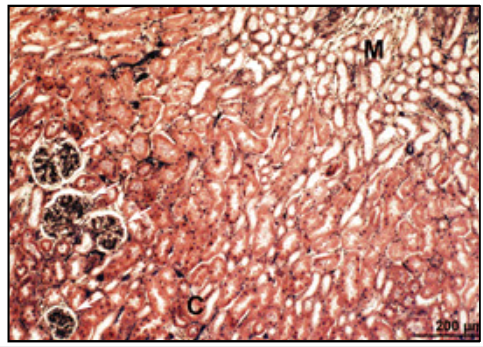

PERIODIC ACID SCHIFF (PAS)

• hexose sugars (complex carbs)

• goblet cell mucins

• cartilage matrix

• glycogen

• basement membranes

• brush border

MAGENTA (DARK PINK)

MICROVILLI/INTESTINAL WITH PAS AND HAEMATOXYLIN

• microvilli with carb. rich GLYCOCALYX

• goblet cells and BM rich in HEXOSE

• stain magenta